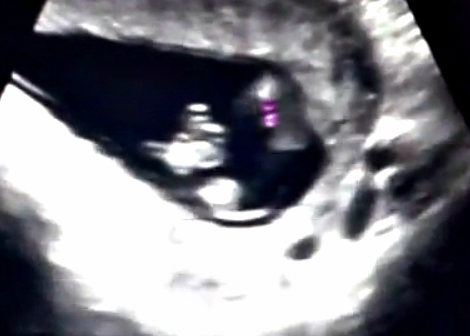

Hi, I'm 15 weeks. Couldn't get a clear idea of gender from my 15 weeks scan. Do you ladies have any idea? Thanks

I saw "something" at one point BUT shes right its not fully "formed" yet. I would give a heavy lean on girl because I didn't see anything definitive otherwise and in several places I can see a very all the way through fork but since I can't see the angle as its a top down shot I can't say 100% But this.... Still very very swollen I can tell why she was hesitant to guess but you are getting a girly from me!!